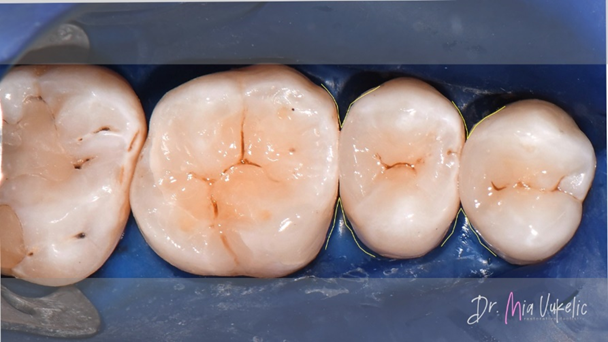

Voor het herstel van de approximale wand werden Halo™-matrixbanden en een Halo™-ring van Ultradent Products gebruikt.

Na het herstellen van de approximale wand werd de restauratie verder laagsgewijs, van buiten naar binnen opgebouwd. De eerste stap bestond uit het aanbrengen van een laag flowable composiet met een dikte van 0,5 mm (Tetric EvoFlow™, Ivoclar*).

Het materiaal dat voor de restauratie werd gebruikt, was Transcend™-composiet (Ultradent Products). De approximale wand werd vervaardigd met de kleurtint EW en de twee daaropvolgende horizontale lagen met de kleurtint A3D. Individuele karakterisering werd verkregen door inkleuring met Kolor + Plus™ kleurmodificator - bruin (Kerr*).